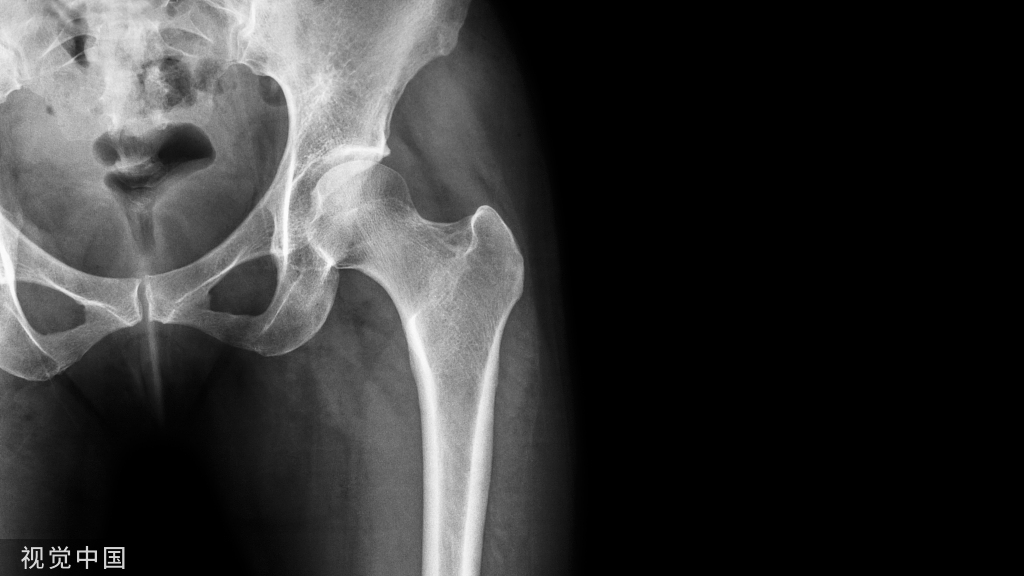

▶▶中心点确立方法

1.由于股骨头是一个相对比较规则的圆形,使用Mose圈或圆规很容易确定股骨头中心。